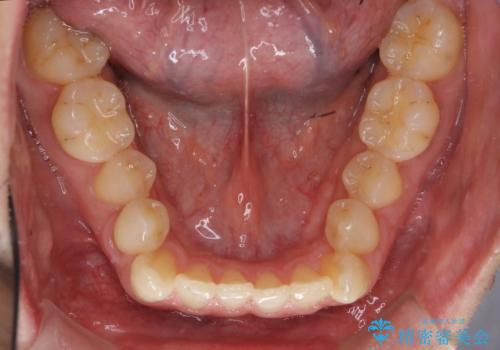

受け口 マウスピースで矯正治療 難易度:中

- 受け口を主訴に来院。

前歯の反対咬合でしたが、かみ合わせが、下顎が大きく前方にずれていました。

引っ込んでいる前歯の前方に下の犬歯が深く咬み込んでおり、また、奥歯のかみ合わせも受け口方向にずれ、骨格性の反対咬合も少々ありました。

上の前歯を前方に出すだけでは治療ができないため、ミニスクリューを用いて下の奥歯を後ろに送っています。

また、下の前歯を0.3mmずつIPRしています。

前歯の反対咬合にしては、難易度は中等度だと思います。

ちょっと前歯を外に出すだけでは治療は難しいです。

下の奥歯を後ろに送るにも、親知らずを抜いたスペース等がなければ難しいです。